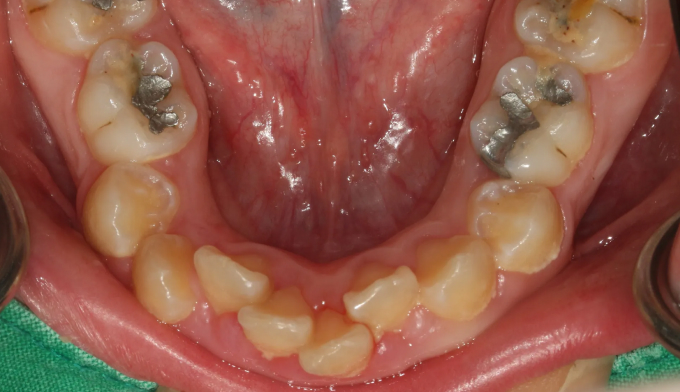

Before

앞니가 돌출되어있고, 특히 전반적으로 양치질이 부족하여 잇몸이 모두 부어있는 상태입니다.

치아들의 배열이 고르지 못한 상태에서는 양치질이 더욱 어려워지므로 구강위생상태에 더 신경을 써야 합니다.